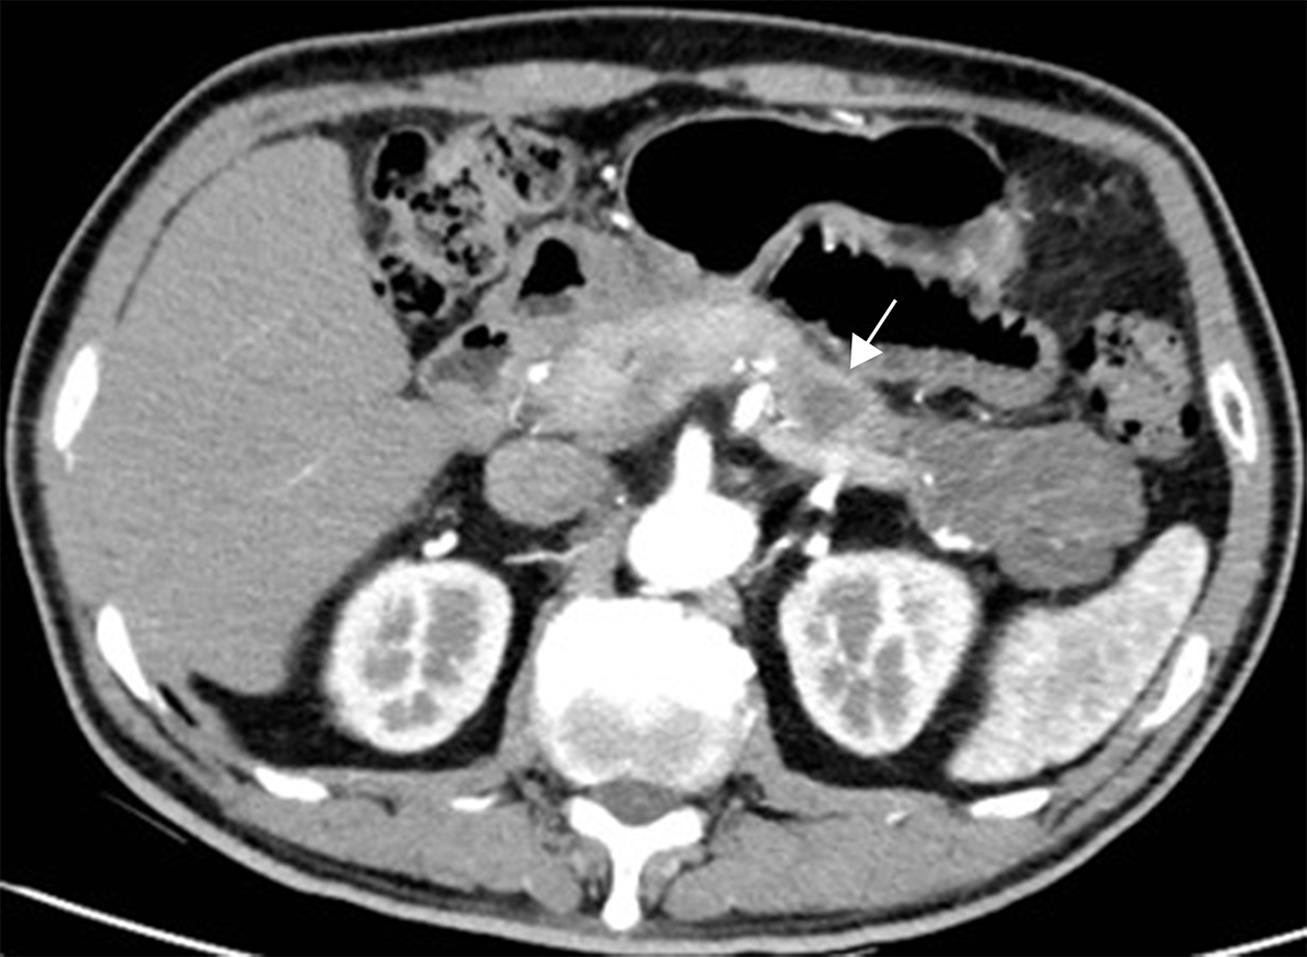

Therefore, this guideline recommends that imaging reports explicitly state whether main pancreatic duct obstruction is present; if so, the location and morphology (stricture versus cutoff) should be clearly described (Fig. 6).

Main-duct intraductal papillary mucinous neoplasm (MD-IPMN).

Fig. 6  Main-duct intraductal papillary mucinous neoplasm (MD-IPMN).

Axial contrast-enhanced pancreatic parenchymal phase computed tomography (CT) image shows an abrupt cutoff of the main pancreatic duct in the pancreatic body (arrow).